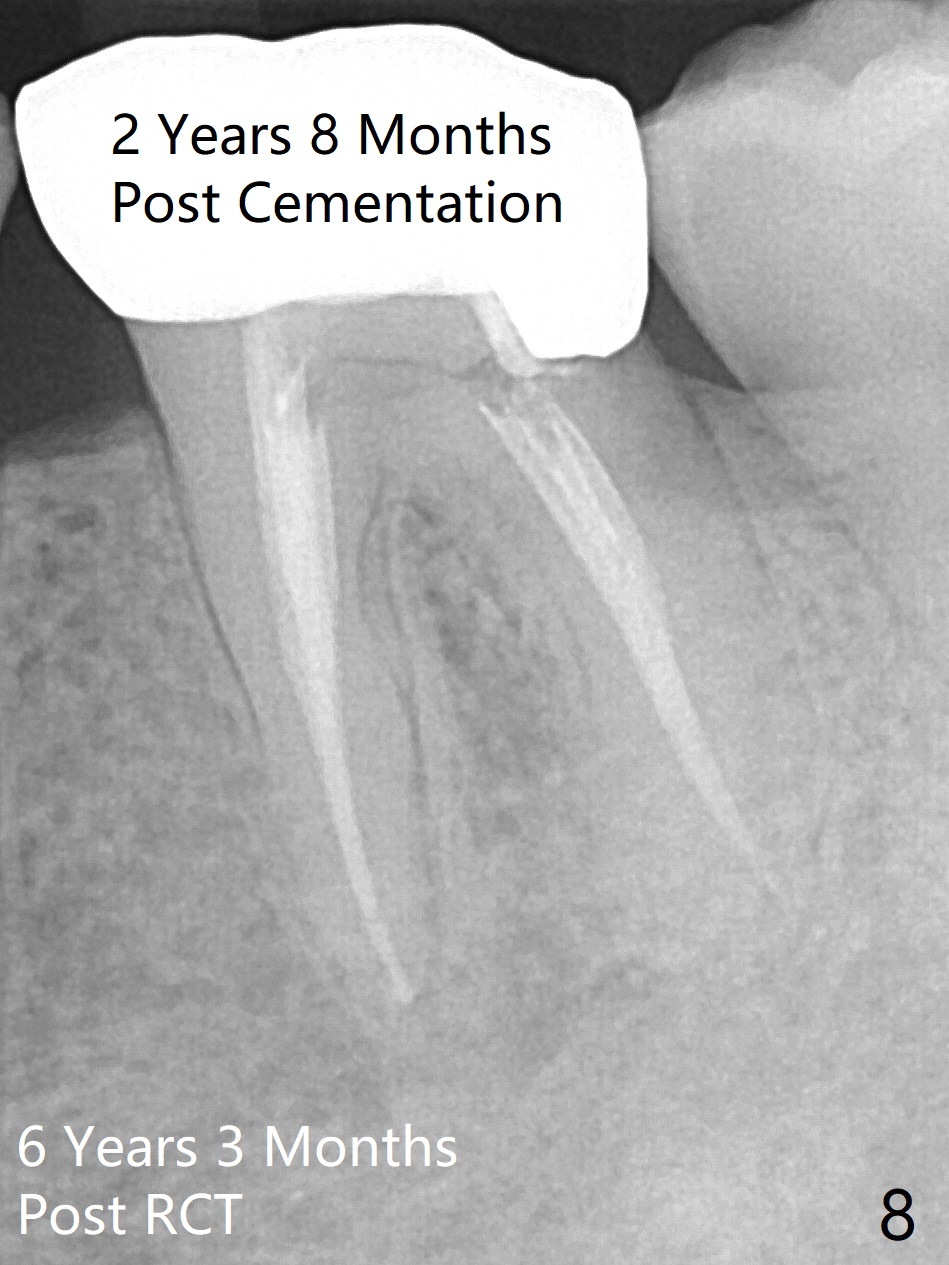

A 29-year-old man has chronic apical perio-dontitis at #19 (Fig.1) for 5 years before RCT with apical buccal swelling (Fig.2). Three days post RCT a fistula develops (Fig.3); curettage is performed. Crown is prepared 3.5 years later (Fig.4). Bitewing is taken immediately before cementation (Fig.5). There is no leakage 2 years 8 months post cementation (Fig.6,7) or periapical radiolucency 6 years 3 months post RCT (Fig.8). Return to Professionals Xin Wei, DDS, PhD, MS 1st edition 11/27/2019, last revision 11/28/2019